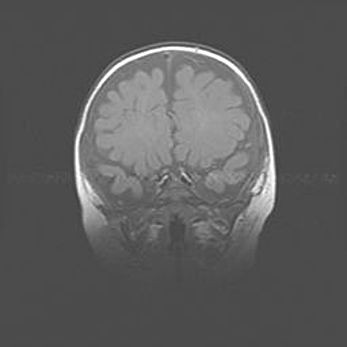

Сообщающаяся гидроцефалия. Кистозная энцефаломаляция головного мозга.

Возраст: 3 месяца 4 дня

Вес: 3100 г

Пол: женский

Окружность головы: 34 см

Срок гестации: 31 неделя

Кистозная энцефаломаляция головного мозга - одна из форм поражения головного мозга в детском возрасте. Характеризуется возникновением множественных и распространённых кист в коре, белом веществе и подкорковых образованиях головного мозга у плодов, новорождённых и детей раннего возраста. Развитие кистозной энцефаломаляции связано с внутриутробной асфиксией и гипотонией, родовой травмой, тромбозом синусов, пороками развития сосудов, инфекциями, сепсисом и другими причинами. Наиболее значимые инфекционные агенты: вирусы простого герпеса, цитомегалии, краснухи, токсоплазмы, энтеробактерии, золотистый стафилококк и другие.